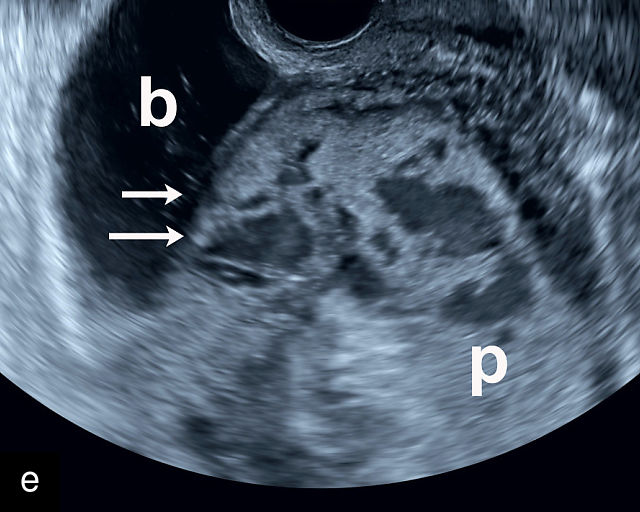

6

Placenta accreta spectrum. (a,b) Sagittal transabdominal grayscale ultrasound of the lower uterus and cervix demonstrating placenta previa accreta, with the placenta (p) containing prominent irregular hypoechoic lacunae. There is absence of the myometrium at the bladder (b) interface (arrows) c, cervix. (c) Sagittal transabdominal color Doppler ultrasound of the lower uterus and cervix demonstrating placenta previa accreta, with increased vascularity of the lower uterus and the myometrial bladder interface. (d) Transvaginal ultrasound of placenta previa accreta showing multiple lacunae involving the cervix with no clear demarcation between the placenta and the cervix. (e) Transvaginal ultrasound of placenta previa accreta showing multiple large irregular lacunae involving the cervix with no clear demarcation between the placenta (p) and the cervix. The placenta has a ‘moth-eaten’ appearance. There is loss of myometrium (arrows). (f) Transvaginal ultrasound of placenta previa accreta without and with color flow Doppler showing multiple large irregular lacunae. The placenta has a ‘moth-eaten’ appearance. There is hypervascularity of the myometrial interface. (g) Transvaginal ultrasound of placenta previa accreta showing multiple lacunae involving the cervix with no clear demarcation between the placenta and the cervix. (h) Transvaginal ultrasound of placenta previa accreta with color flow Doppler showing hypervascularity of the myometrial interface and irregularity of the bladder wall. b, bladder; p, placenta. (i) Transabdominal grayscale ultrasound of cesarean scar pregnancy. The uterine fundus (f) is empty (arrowhead). The gestational sac (arrow) is located in the lower uterus, anterior to the uterine canal, and lies above the cervix (c). b, bladder. (j) Transvaginal grayscale ultrasound image of cesarean scar pregnancy showing the empty fundus (f) and the normal cervix (c). The gestational sac lies below the fundus, above the cervix and anterior to the uterine cavity. (k) Transvaginal grayscale ultrasound image of cesarean scar pregnancy showing the empty cavity (arrowheads) of the uterine fundus (f), and the normal cervix (c). The gestational sac lies below the fundus, above the cervix and anterior to the uterine cavity (arrow).

Several characteristic sonographic findings are associated with PAS.90,95,96,97 These include placental lacunae, which appear as hypoechoic, irregular spaces within the placenta with high-velocity turbulent flow on color Doppler.16,50 Other features include obliteration of the retroplacental clear space, thinning of the myometrium in the lower uterine segment, irregularity and hypervascularity of the myometrial–bladder interface, and placental bulging into the bladder (Figure 6a–h).90,96,98,99